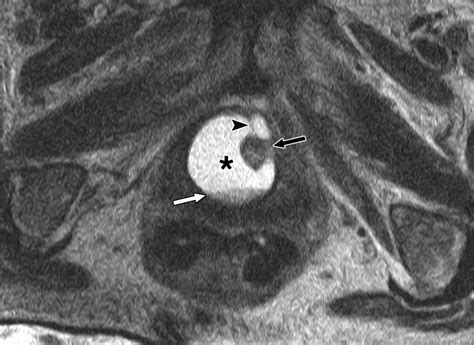

Diagnosis requires a high index of suspicion, especially when standard treatments for UTIs fail. A physician will typically perform a physical exam, which may reveal a tender mass along the anterior vaginal wall. If pressure is applied to the mass, it is not uncommon for a small amount of urine or purulent discharge to exit the urethra.

MRI (Magnetic Resonance Imaging) The gold standard for visualizing the size and location of the diverticulum.